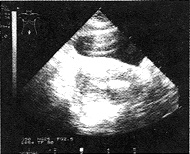

2.方法:宫腔镜电切手术均以5%葡萄糖液进行灌流,采用超声双项对比法监视手术过程,即充盈膀胱及向子宫腔内注入灌流液,子宫内壁在高频电热作用下形成强回声光带,此为特征性的声像图改变,是超声监视腔内电切术的指征;同时,灌流液和组织受热汽化的气体渗入肌壁呈云雾状强回声,形成特殊超声影像(附图),即提示有腺肌症可能。于镜下见切面有淡粉色组织处,用5 mm的环形电极切下该处的肌壁组织(子宫壁的取材部位距内膜≥1 mm),长2.5~3.0 cm、宽0.5 cm、厚0.5 cm,10%福马林固定,HE染色,行光镜下病理检查。根据一个低倍视野中所见腺体的多少,将腺肌症肌层受侵的程度分为:轻度:可见1~3个腺体;中度:可见4~9个腺体;重度:可见10个腺体以上。

附图 子宫内壁在高频电热作用下形成强回声光带,灌流液和组织受热汽化的气体渗入肌壁呈云雾状强回声,尤以前壁为著